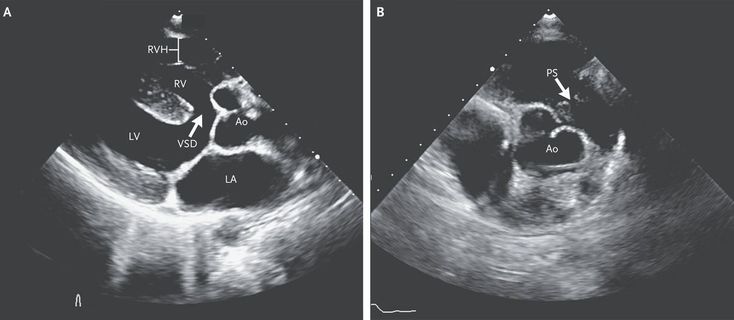

A 29-year-old man who had recently immigrated to the United States presented to the cardiology clinic with worsening exertional dyspnea, visual blurring, and headaches. These symptoms had been present since childhood, but he had not received regular medical care and the condition had not been diagnosed. The patient had found that his symptoms lessened when he squatted or after 30 minutes of rest. The oxygen saturation was 92% while the patient was breathing ambient air. The physical examination was notable for a harsh holosystolic murmur at the left sternal border (listen to audio) with a sternal heave. There was no evidence of digital clubbing. Electrocardiography showed sinus rhythm with a right bundle-branch block. Laboratory studies showed a hemoglobin level of 20 g per deciliter (reference range, 13 to 17). Echocardiography (Panel A) showed the aorta (Ao) overriding a large ventricular septal defect (VSD) and right ventricular hypertrophy (RVH), along with subpulmonic stenosis (PS) (Panel B), all of which confirmed the diagnosis of tetralogy of Fallot. The characteristic murmur is due to right ventricular outflow obstruction. Squatting maneuvers increase systemic vascular resistance, resulting in reversal of shunting at the ventricular septal defect and therefore a reduction in symptoms. The patient underwent surgical repair including pulmonary valvotomy, closure of the septal defect, resection of muscle bundles in the right ventricular outflow tract, and patch augmentation of the infundibulum and main pulmonary artery. Two months later, he was recovering well without further episodes of dyspnea, visual disturbance, or headache.